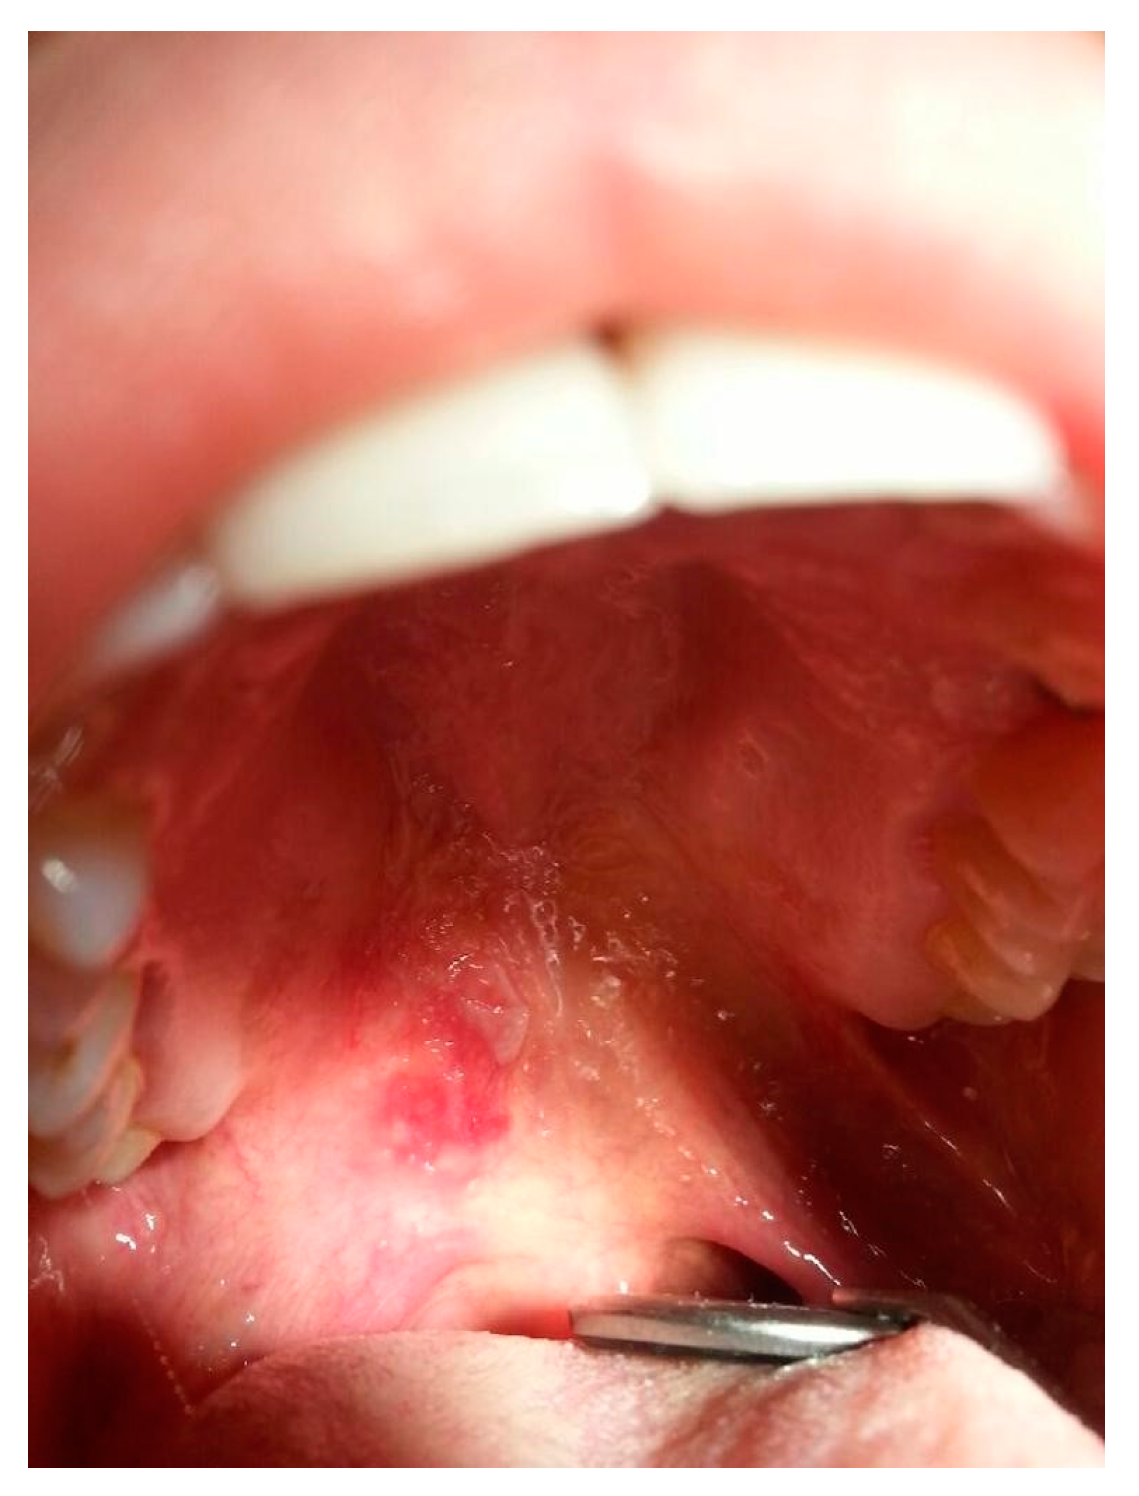

Oral mucosa involvement is found in 3–25% of CLE cases [126]. Mucosal lupus commonly presents as white papules forming a tree-like pattern, erosions and ulcers (Figure 9) affecting buccal and gingival mucosa or the red zone of the lips. Involvement of the genital mucosa is rarely reported. Lesions are usually observed in mechanically irritated sites. They are usually symptomless but seldom may cause mild hypersensitivity and dryness of the oral cavity [18,126]. Furthermore, the available literature includes numerous case reports of squamous cell carcinoma development within mucosal lupus lesions, especially in the red zone of the lips [127,128,129,130,131,132,133,134].

Figure 9.

Mucosal SLE. Erosions on erythema lesions.

For instance, mucous membranes may be affected in DLE, and in cases of the buccal mucosa involvement, it may resemble lichen planus (LP) and oral leukoplakia, but the main distinguishing features are the radial arrangement and brush-like distribution with central erythema [84]. Genital involvement is rare [72]. In the differential diagnosis of the mucosal DLE histopathological criteria established by Lever are hyperkeratosis, atrophy of the Malpighian layer, hydropic degeneration of the basal cells, lymphoid cell infiltrate, features of edema and vasodilatation [135]. Another disorder in whose clinical picture mucosal lesions are observed is DLE/LP overlap syndrome [9].